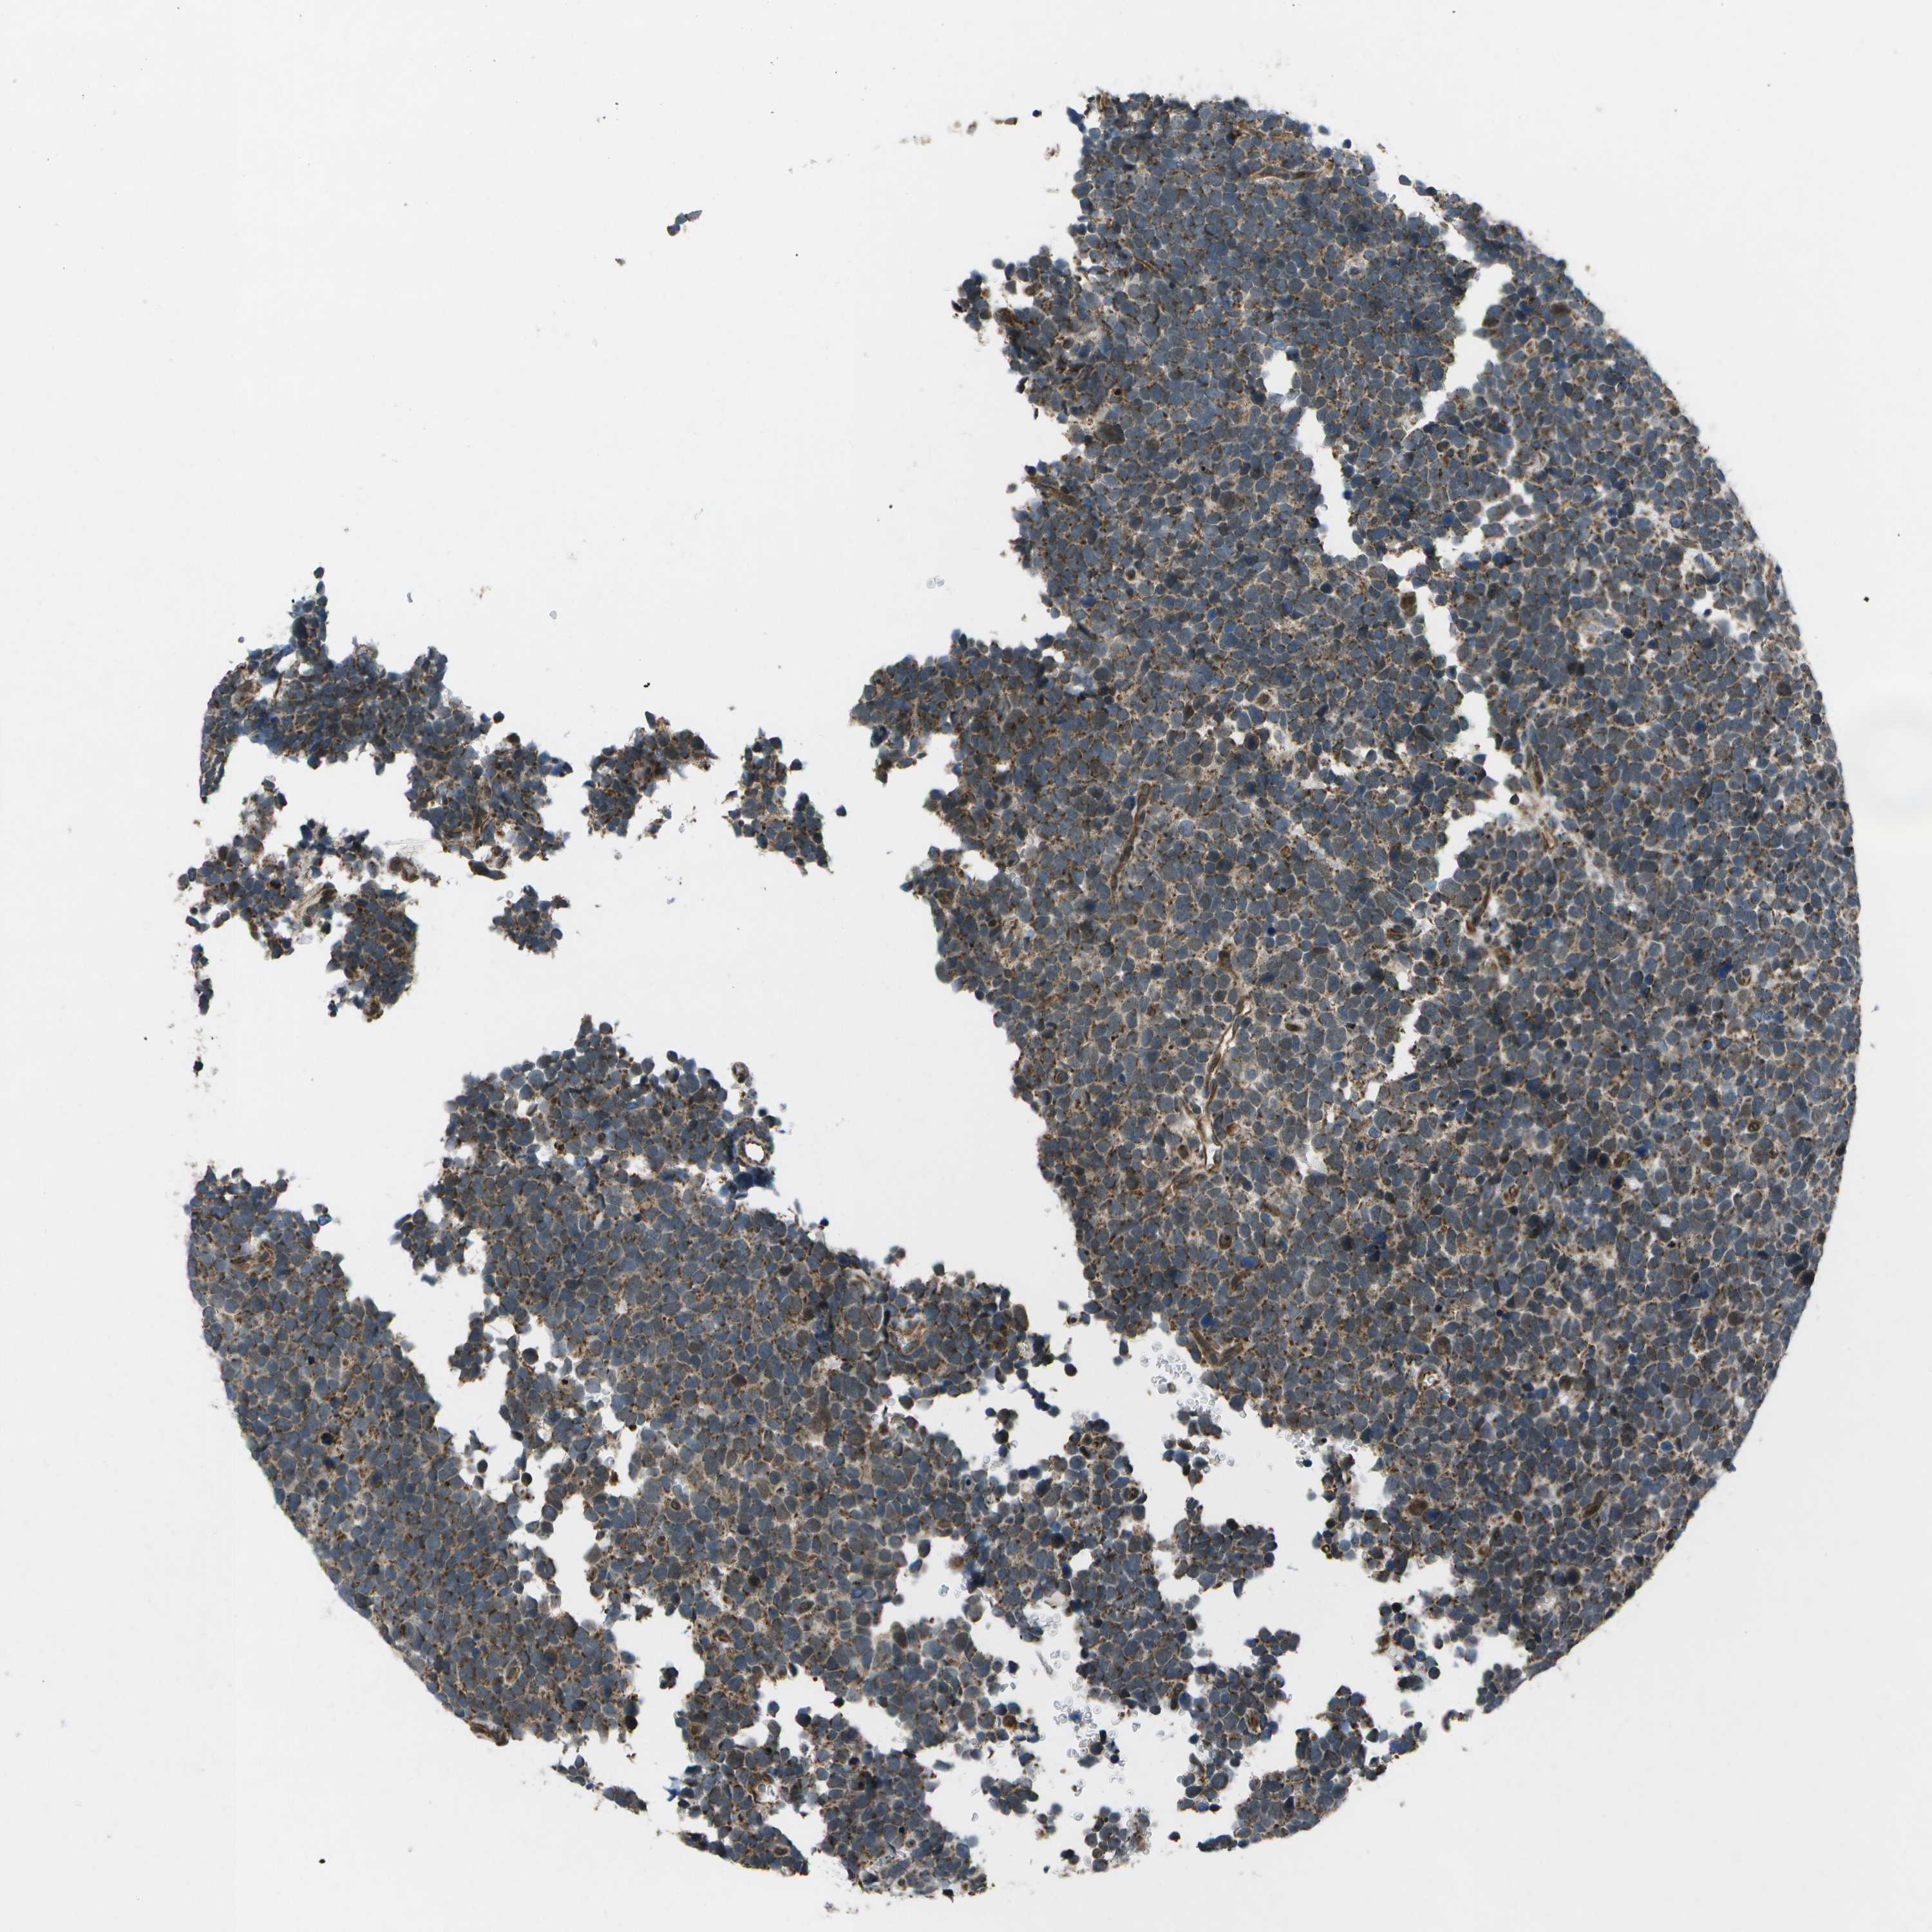

UROTHELIAL CANCER - Protein expressioni

A mouse-over function shows sample information and annotation data. Click on an image to view it in a full screen mode. Samples can be filtered based on level of antibody staining by selecting one or several of the following categories: high, medium, low and not detected. The assay and annotation is described here.

Antibody stainingi

Antibody staining in the annotated cell types in the current human tissue is reported as not detected, low, medium, or high, based on conventional immunohistochemistry profiling in selected tissues. This score is based on the combination of the staining intensity and fraction of stained cells.

Each image is clickable and will lead to virtual microscopy that enables deeper exploration of all samples and also displays staining intensity scores, fraction scores and subcellular localization as well as patient and tissue information for each sample.

Antibody HPA016496

Antibody CAB022082

Staining

High

Medium

Low

Not detected

Intensity

Strong

Moderate

Weak

Negative

Quantity

>75%

75%-25%

<25%

None

Location

Nuclear

Cytoplasmic/membranous

Cytoplasmic/membranous,nuclear

Urothelial carcinoma, Low grade

Urothelial carcinoma, High grade